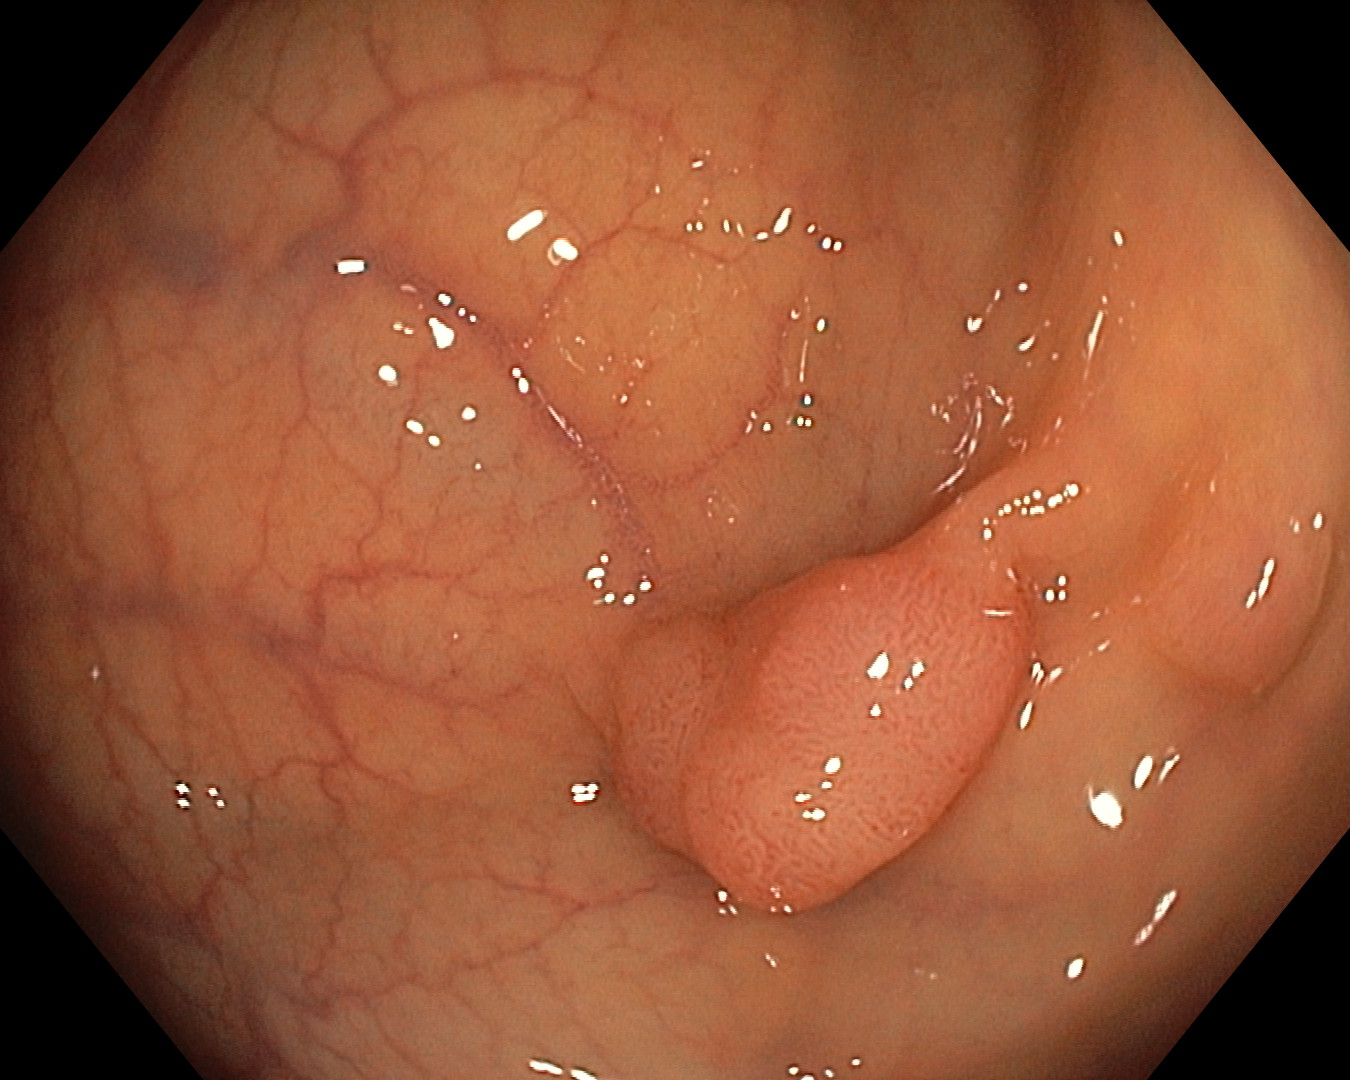

Bitno je napomenuti da su ove napredne slikovne metode (digitalno uvećanje slike i prikaz pod uskopojasnim spektrom), naročito korisne u endoskopskoj analizi polipa kolona. Ovdje u većini slučajeva nije potrebna dodatna patohistološka analiza, čime se ubrzava postupak dijagnostike, uz financijske uštede sa strane pacijenta

Prikaz polipa kolona pod normalnim svjetlom | Prikaz polipa kolona u uskopojasnom spektru |